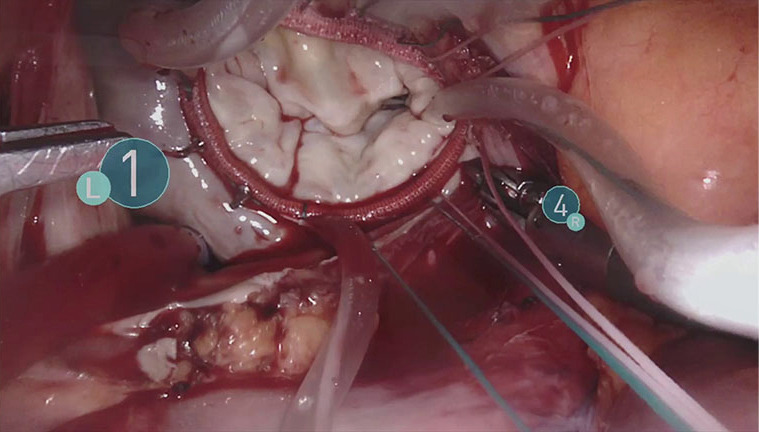

Figure 4.

Mitral valve appearance before annuloplasty.

Figure 5.

Mitral valve after plasty. We can see some residual sutures before the use of Cor-Knot fasteners.